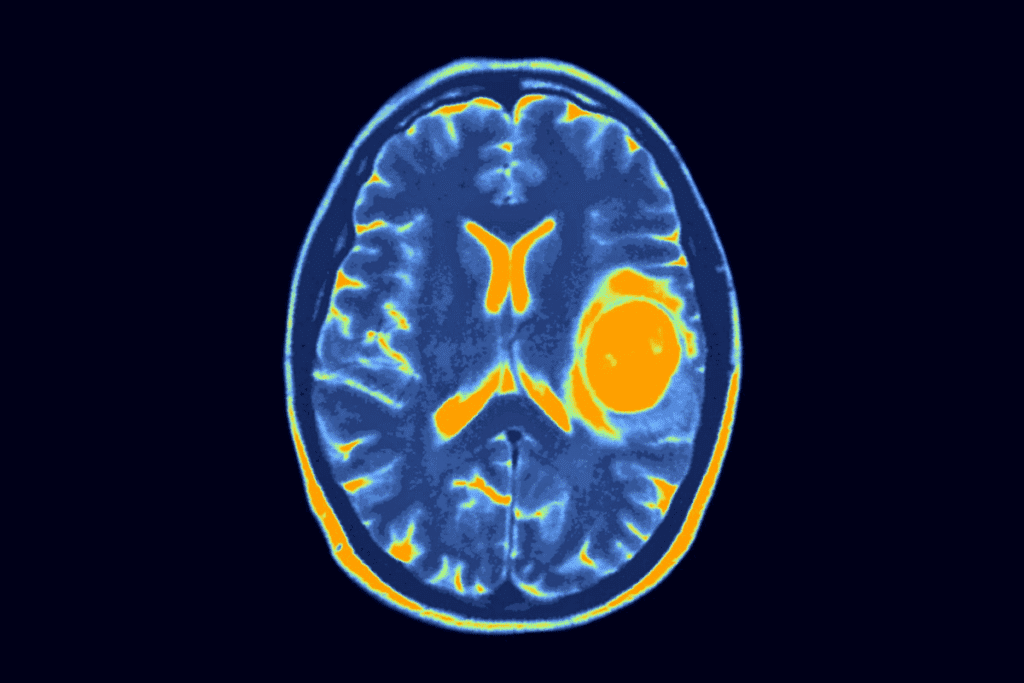

How are pediatric brain tumors diagnosed?

Diagnosis involves imaging tests like MRI or CT scans. A biopsy is then done to confirm the tumor type. Our team works with families to get a quick and accurate diagnosis.